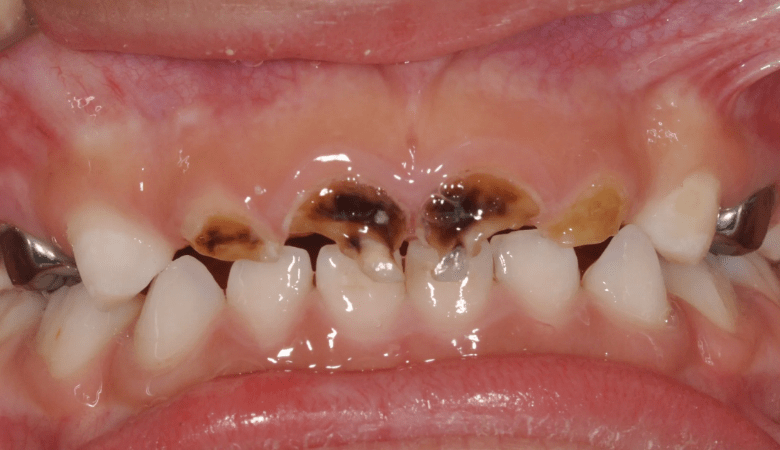

Sún răng là tình trạng men răng bị tổn thương và mòn dần do tác động của axit, thường hình thành từ vi khuẩn trong mảng bám răng kết hợp với đường từ thức ăn. Quá trình này diễn ra từ từ, ban đầu chỉ là những đốm trắng đục trên bề mặt răng, sau đó chuyển sang màu vàng hoặc nâu, cuối cùng tạo thành lỗ hổng trên răng. Sún răng khác với sâu răng ở chỗ nó thường xuất hiện ở nhiều răng cùng lúc và lan rộng hơn trên bề mặt răng, trong khi sâu răng thường khu trú ở một điểm.

Sún răng là tình trạng men răng bị tổn thương và mòn dần do tác động của axit (Nguồn: Internet)

- Xuất hiện các đốm trắng đục hoặc vàng nâu trên bề mặt răng: Đây là dấu hiệu sớm nhất của sún răng. Các đốm này thường xuất hiện ở cổ răng, gần nướu.

- Răng bị mòn, cụt: Khi tình trạng sún răng tiến triển, răng sẽ bị mòn dần, đặc biệt là ở rìa cắn của răng cửa.

- Răng bị đen, có lỗ: Nếu không được điều trị, các đốm trắng sẽ chuyển sang màu đen và hình thành các lỗ sâu.

Sún răng thường xuất hiện ở nhiều răng cùng lúc, lan rộng trên bề mặt răng và có màu vàng hoặc nâu. Trong khi đó, sâu răng thường khu trú ở một điểm, có màu đen và ăn sâu vào bên trong răng.